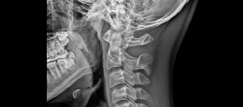

목디스크는 디스크라는 뼈와 뼈 사이의 공간에 위치한 수핵이 나와 경추 신경을 압박하여 발생하는 질환입니다. 목디스크는 인체의 다른 부위에 비해 가장 많이 발생하는 질환이며, 나이가 들면서 더욱 빈번하게 발생하게 됩니다. 이번 글에서는 목디스크의 증상 3가지를 알아보겠습니다.

경추신경이 압박되면 신경의 전기 신호가 잘 전달되지 않아 저림 현상이 발생할 수 있습니다. 이는 손가락이나 팔, 어깨, 목 등 신체의 다른 부위에서도 느껴질 수 있습니다. 또한, 신경의 손상이 심한 경우, 팔과 다리를 움직이는 것이 어렵게 될 수 있습니다.